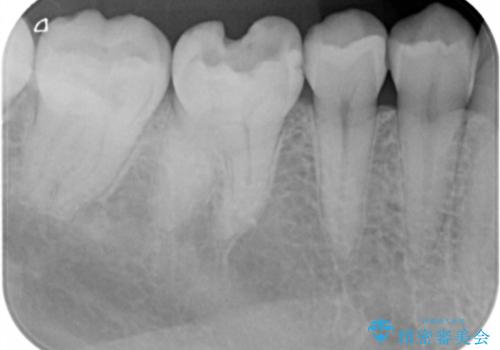

- 右下6番のメタルインレー脱離のため来院。

セラミックの治療を希望されたため切削量を考慮し、セラミックインレーでの治療を選択しました。

う蝕が深くまで進行していたので、CRで裏層した上で形成・印象をしています。